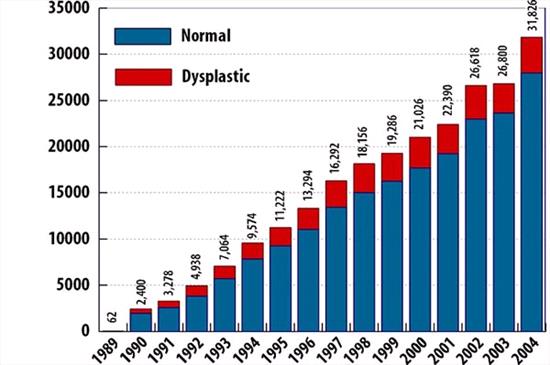

| Normal versus Dysplastic Elbows, 1989 - 2004 |

OFA's Elbow Dysplasia Database

From 1989 through 2004, 235,048 dogs were submitted to the OFA elbow database for evaluation. 234,958 were found to be normal. 35,790 dogs (15.23%) were found to be dysplastic. 732 dogs had equivocal results (not represented in this chart). In 2004, 3,854 of the 31,848 dogs tested were found to be dysplastic, 12.10%. |